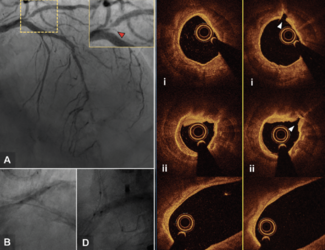

Ruth Newcombe; Timothy Glenie, MBChB; Ali Khan, MBBS, MD; Bernard Wong, MBChB; Aleksandar Cicovic, MBChB; Guy Armstrong, MBChB; Seif S. El-Jack, MBBS, MD

This first case series presents the use of Shockwave Intravascular Lithotripsy in a patient with LMCA disease with multivessel disease who declined surgery, a patient with isolated LMCA disease and severe cardiomyopathy, and a late...